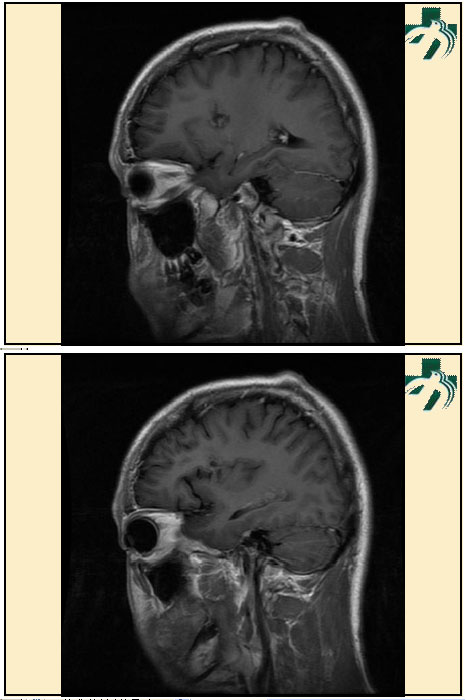

奴卡氏菌感染

第九期三博

读片会

病例之四

北京协和医院 提供

男性,22岁。自觉虫咬后皮疹、肢体麻木4月